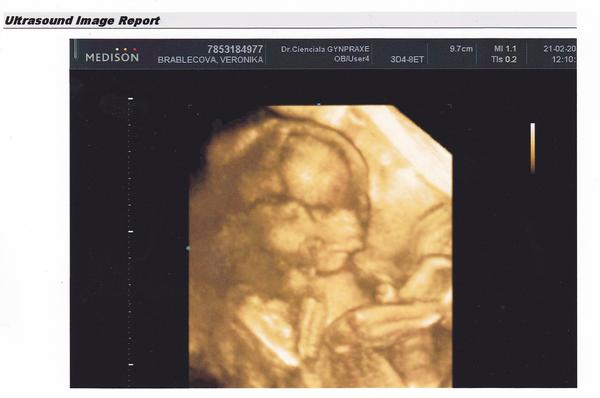

@lucikk1 @suzik161 holky díky moc.... já jsem celá z toho v prdeli 😀 😀 fakt to se ani popsat nedá 🙂 hooooodně moc vám to taky přeju zažít, ale taky se dočkáte, nebojte nic. A jak tam má ty ruce a nožky fajné na té první fotce, no krása.... no a tak jsem byla naměko dneska, že jsem si řekla, že když už se chlapovi nevyplnil ten kluk, tak že aspoň bude jméno, jaké se mu nejvíce líbí... takže s největší pravděpodobností to bude Eliška 🙂